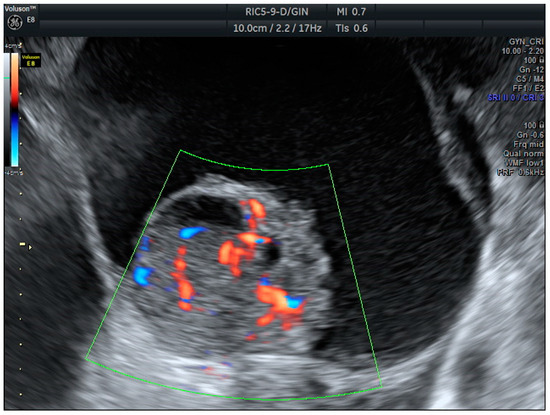

Years later, in 2008, the IOTA Simple Rules (SR) were among the first systems to provide a standardized framework for classifying adnexal masses based on ten rules. The benignity features (B) included unilocular cysts (B1) solid components < 7 mm (B2), acoustic shadows (B3), regular multilocular tumor < 100 mm (B4), and negative color maps (B5). The malignancy features (M) contained irregular solid tumors (M1), ascites (M2), ≥4 papillae (M3), multilocular irregular solid tumors > 100 mm (M4), and high vascularization (M5) (Figure 1 and Figure 2). According to SR, masses are classified as malignant if one or more malignancy features are present and no benignity features are observed; benign if one or more benignity features are present and no malignancy features are observed; and inconclusive if both types of features or none are present [5]. These rules have been extensively validated in the literature and have been shown to have good diagnostic performance [6,7]. In 2016, the IOTA Simple Rules Assessment was developed, integrating the Simple Rules with the consideration of whether the patient was treated at an oncology center, improving diagnostic accuracy [8], and adding a percentage of the probability of malignancy.

Figure 2. Serous caricinoma. Multicystic mass with a solid papilla inside with a high score Doppler color (score color 4).